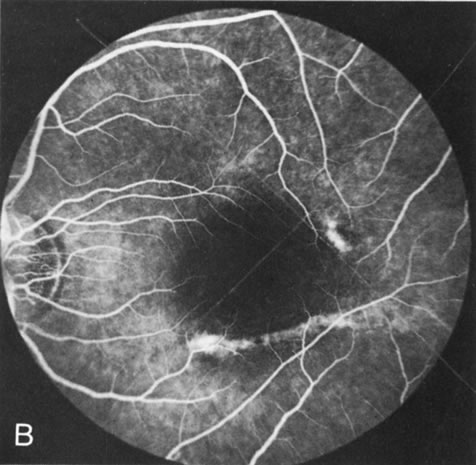

Generalized choroidal dystrophy is usually noted in middle-aged mildly symptomatic individuals who show a predominantly peripapillary or pericentral distribution of choroidal atrophy. Gradually, over the years these areas enlarge to eventually involve the entire retina. These changes are vividly seen on FA (Fig. 6).

Fig. 6. Generalized choroidal dystrophy. This 65-year-old woman gradually developed enlarging, progressive areas of choroidal atrophy over a 20-year period. When initially seen, the abnormalities were confined to the peripapillary and macular region (A,B). In a recent examination, the generalized choroidal atrophy is vividly demonstrated on angiography (C–F).